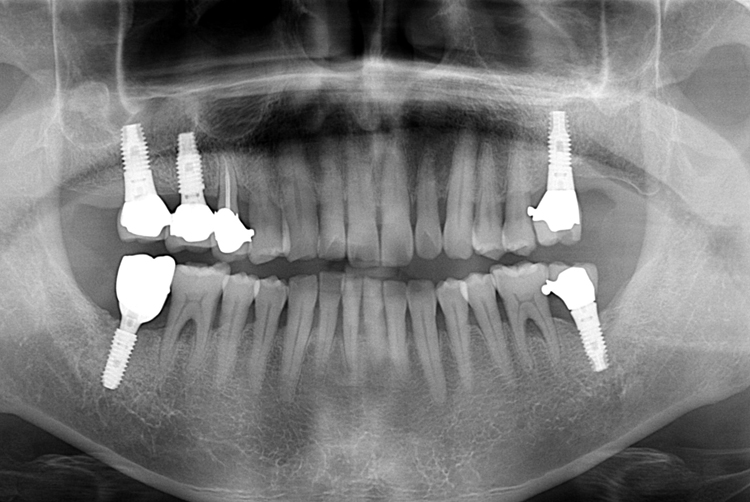

[임플란트] 어금니 임플란트

치료전 : 2018-09-20